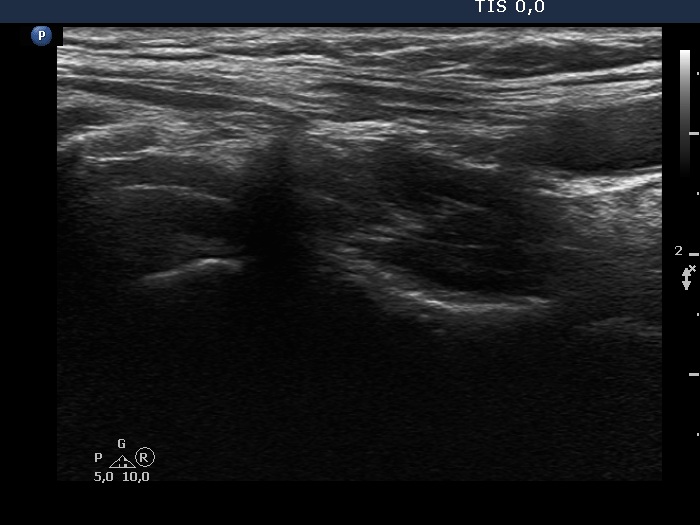

The operated thyroid - case 2055 (ultrasonographic picture 2)

Right lobe, longitudinal view.